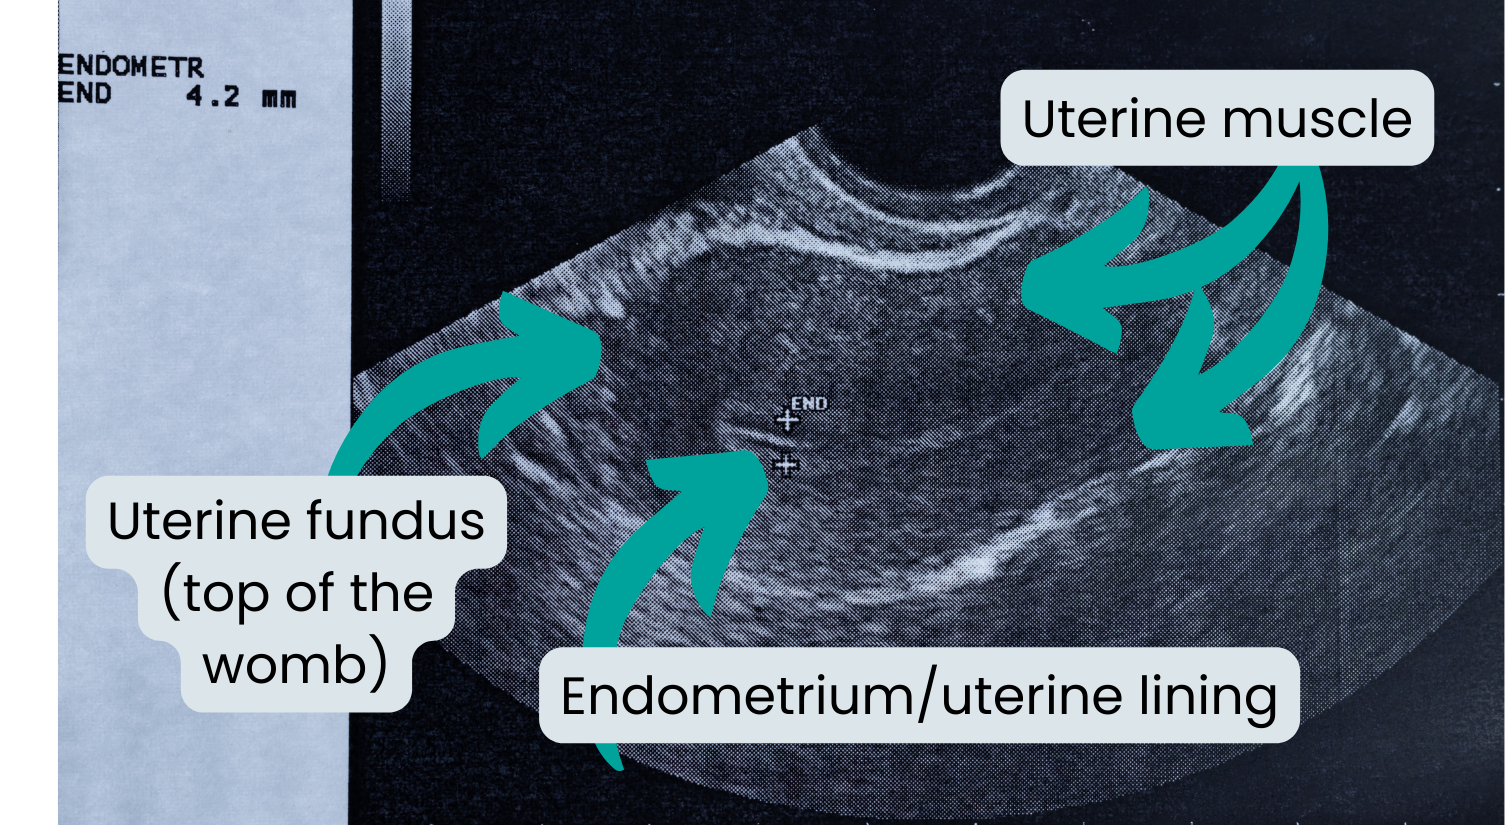

Ultrasound scan

Ultrasound scans are commonly done to investigate abnormal vaginal bleeding.